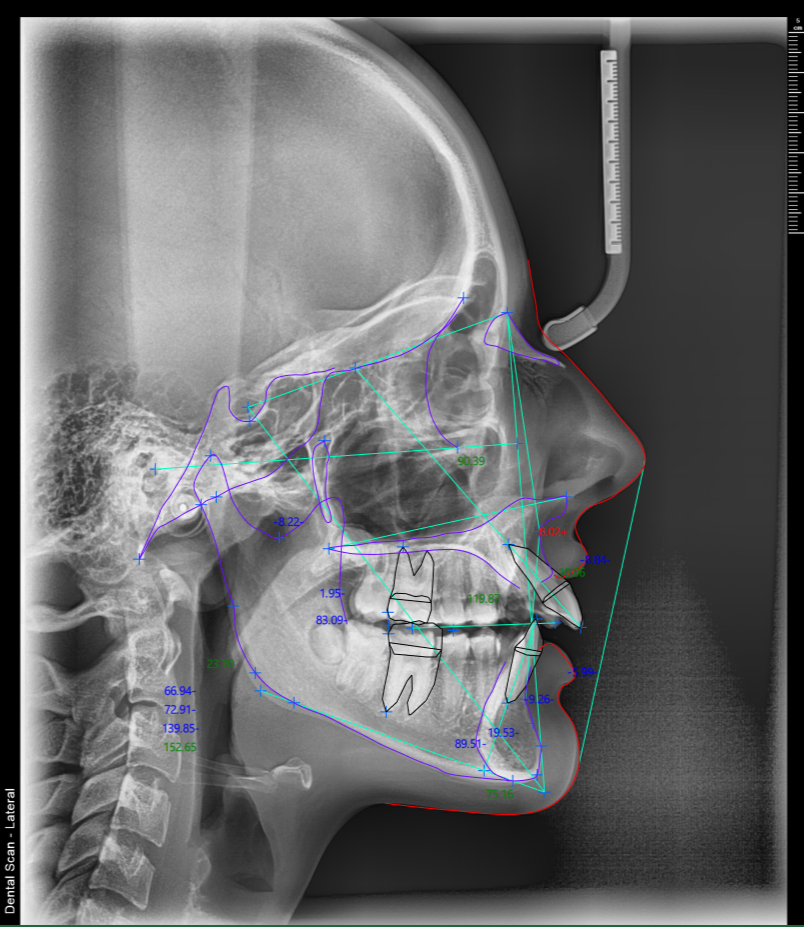

Orto analize uz lateralni cefalogram

U Dental Scan centru, uz svaki lateralni cefalogram nudimo širok spektar standardizovanih i naprednih ortodontskih analiza, prilagođenih savremenim protokolima planiranja terapije.

Precizna cefalometrijska analiza za pouzdanu procenu skeletnih, dentalnih i mekotkivnih odnosa, kao i jasnu osnovu za izbor terapijske strategije.

Na raspolaganju su sledeće ortodontske analize:

- AMC I

- AMC II

- Beijing

- Burstone

- Downs

- Jarabak

- Jefferson

- Kim

- McNamara

- Method I

- Method II

- Riketts

- Steiner

- Tweed

- Wylie

Jedan snimak – kompletna ortodontska dijagnostika

Sve analize se izrađuju digitalno, uz visoku preciznost merenja i jasan grafički prikaz, što omogućava lakšu interpretaciju i sigurnije donošenje kliničkih odluka. Unapredite Vaše planiranje ortodontske terapije, praćenje napretka i profesionalnu komunikaciju sa pacijentima.